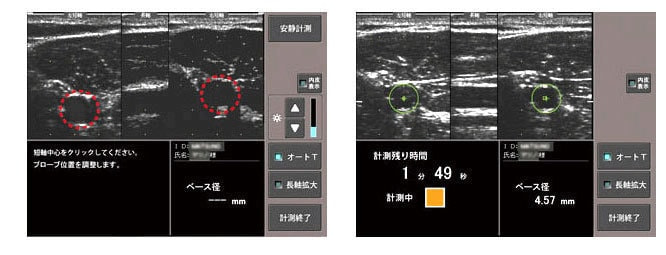

■画面上の動脈短軸をクリックするとプローブの位置が最適に調整されます

■安静時径測定後は、駆血ボタンを押すだけ

駆血カフは最適圧で加圧され、自動で圧力を保持します。

■計測終了を、アナウンスでお知らせします

計測の手順